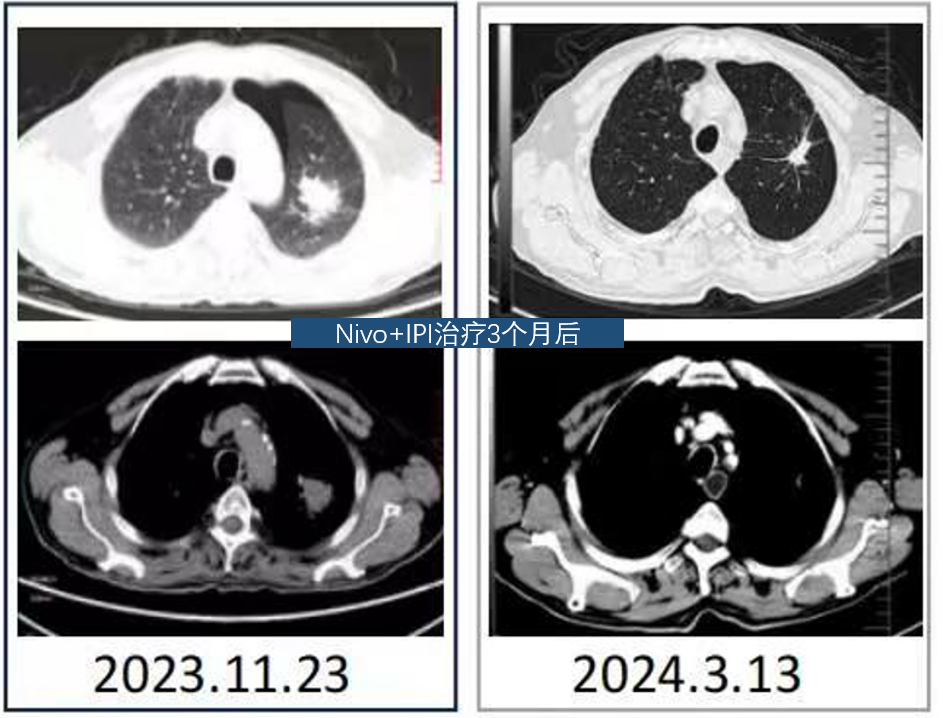

疗效评价

影像学复查,疗效评价PR(缩小63.6%)

4.png

影像学复查(持续PR),PFS超过24个月

5.png

刘克军教授:本病例为一位 75 岁的高龄患者,确诊为 IVB 期左肺腺癌,伴双侧肾上腺转移。分子病理提示 EGFR/ALK 阴性,KRAS G12C 突变,PD-L1 阳性。鉴于患者高龄、家属对化疗耐受性的担忧以及对生活质量的诉求,经过慎重评估,选择 “纳武利尤单抗+伊匹木单抗”的双免一线治疗方案。结果显示,患者在治疗 3 个月后即达到部分缓解(PR),病灶缩小幅度超过 60%。截至目前,患者PFS超过24个月,且仍处于持续缓解状态,生活质量优异,实现了晚期肺癌的“慢病化”管理。这一成功案例不仅是精准医疗的体现,也为临床处理高龄复杂病例提供了宝贵的参考。